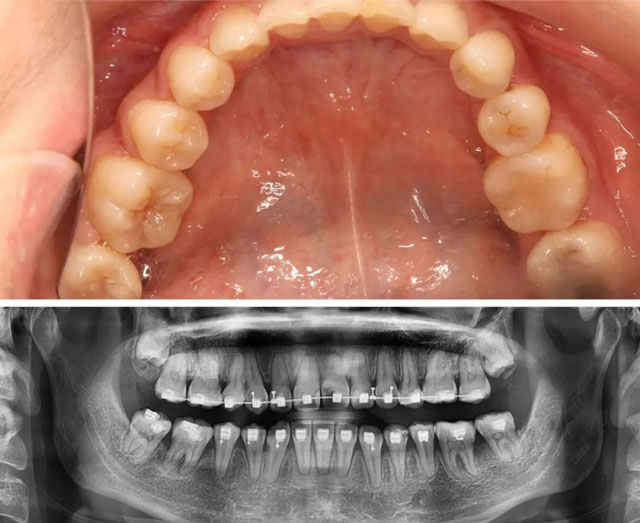

口內(nèi)照片及全景片(2021年2月)

口內(nèi)照片及全景片(2023年11月)